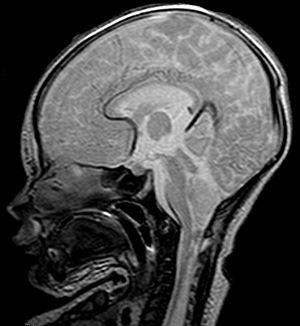

Malformación de Chiari

Esta malformación hace referencia a una condición del cuerpo en la que los tejidos propios del cerebro están ubicados en el mismo canal de la médula espinal. Esta afección se puede producir desde el mismo nacimiento, o bien ser una afección congénita que se irá desarrollando con el paso del tiempo.

Los síntomas de la malformación de Chiari son bastante graves: dolor agudo en la zona del cuello, sensación punzante (debido a la comprensión que experimentarán las terminaciones nerviosas comprendidas en la zona superior del cuello y de la columna vertebral), o bien la interrupción del torrente sanguíneo, lo que hará que sea imposible que llegue a ciertos puntos durante momentos puntuales.